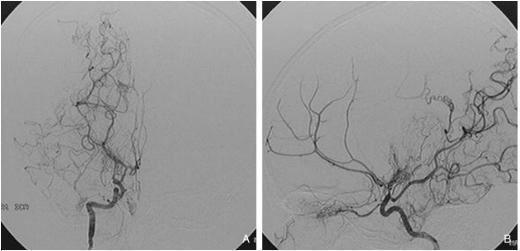

치료는 크게 약물 치료와 수술적 치료로 나뉩니다. 약물 치료는 주로 뇌경색 예방에 초점을 맞추고 있으며, 항혈소판제 등이 사용됩니다. 수술적 치료는 혈관우회술을 포함하여 뇌의 혈류를 개선하고 혈역학적 안정을 도모하는 데 목적이 있습니다. 최근 연구들은 수술적 치료가 뇌출혈 발생률을 감소시키고 장기적인 생존율을 향상시킬 수 있다는 결과를 보여주고 있습니다.